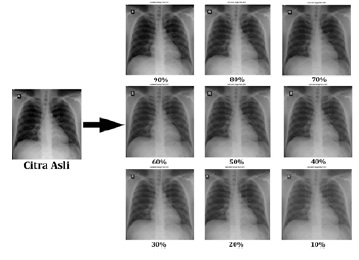

Analisis Kualitas Citra Medis Terkompresi JPEG

Derry Suia Pathentantama, I Made Oka Widyantara, Rukmi Sari Hartati

xxxxx

• PDF12 (English)